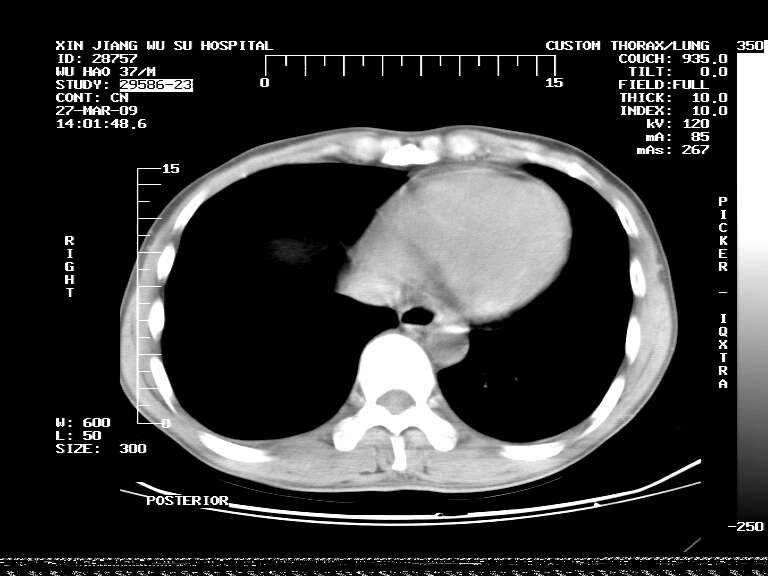

男,37岁,体检胸透发现阴影。

患者体检发现 无症状 左肺下叶占位,边缘模糊,可见血管聚束、分叶、胸膜牵拉,增强呈不均匀性强化。 首先考虑左肺下叶周围型肺癌,建议穿刺活检。

患者体检发现 无症状 左肺下叶占位,边缘模糊,可见血管聚束、分叶、胸膜牵拉,增强呈不均匀性强化。 首先考虑左肺下叶周围型肺癌,建议穿刺活检。支持!

左肺下叶见一结节病变,边缘欠清不光滑,与胸膜粘连且胸膜局限性增厚,注药后呈环形强化,动脉期壁呈明显点环状强化,静脉期壁强化减低,中心密度低无强化,灶周无明显的卫星灶和水肿区(晕征)---考虑周围性肺癌,不除外感染性病变,建议穿刺活检。

周围有卫星灶,胸膜反应不明显,病灶中心有坏死。建议先抗结核治疗后,短期复查